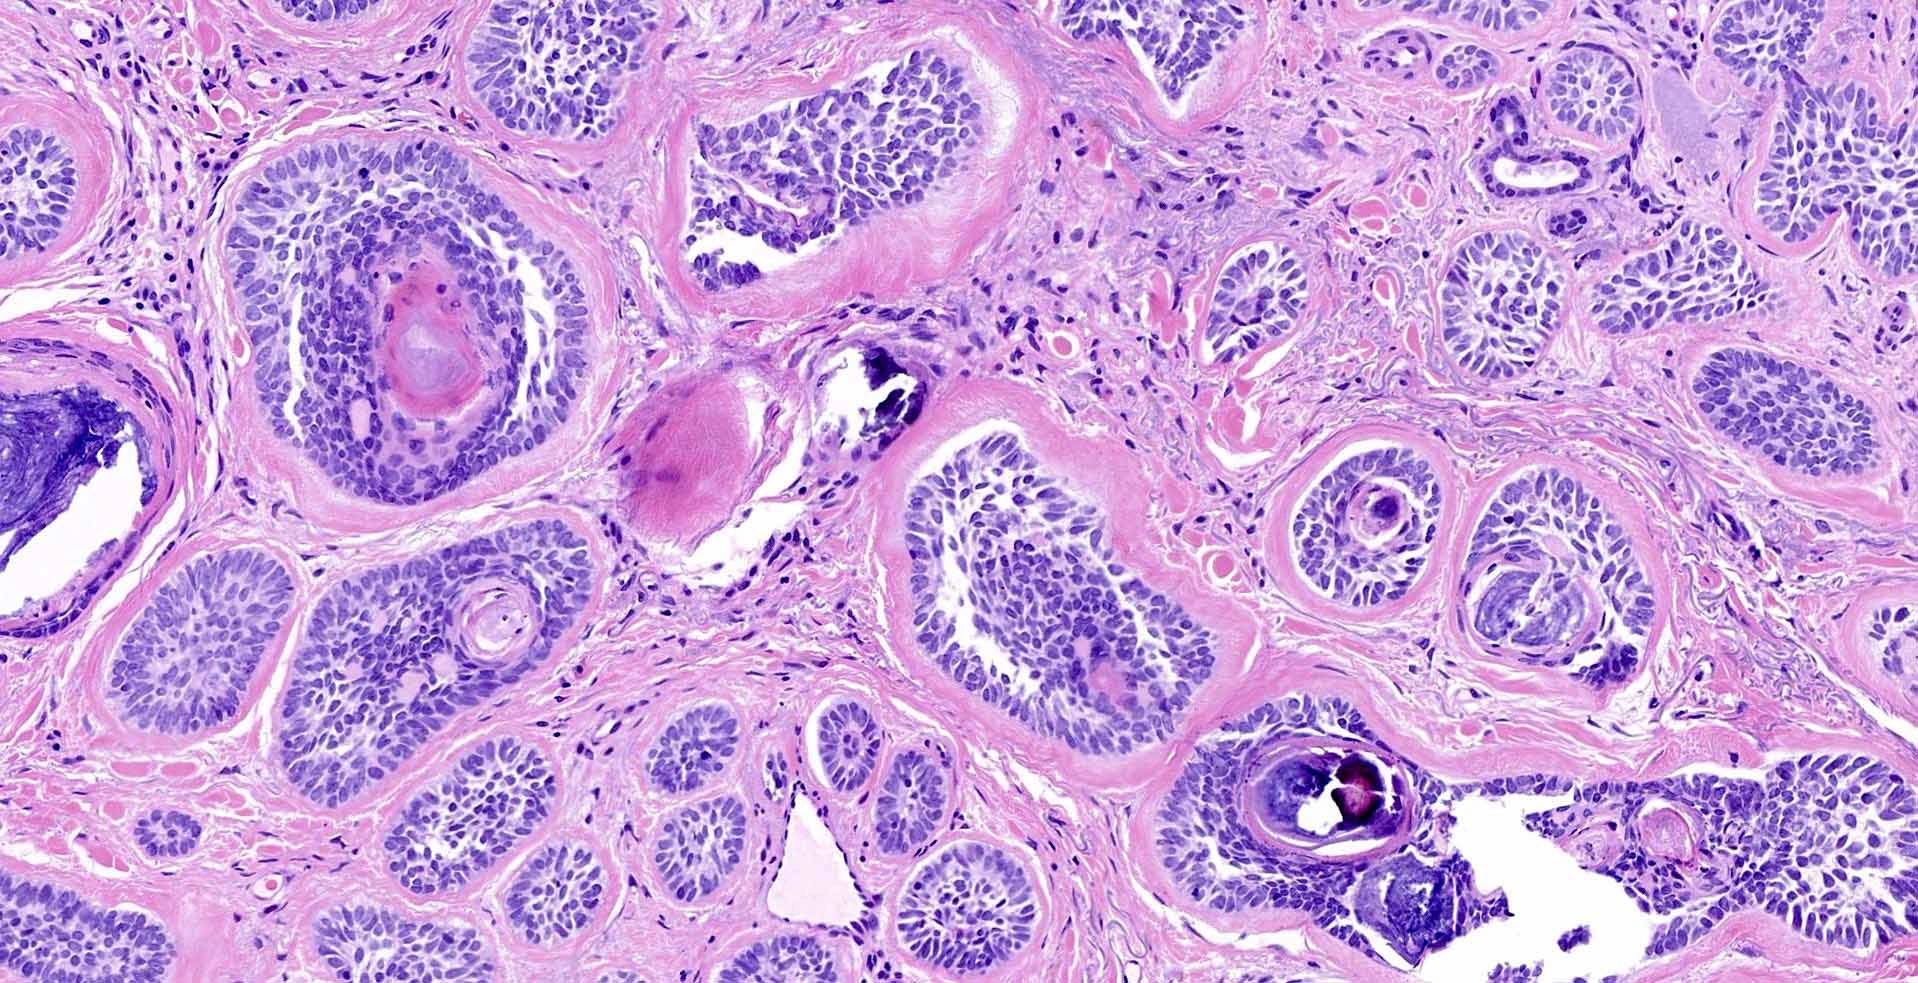

Аденокарцинома — це особливий тип злоякісної пухлини, яка виникає з залозистого епітелію та може вражати різноманітні органи: шлунок, товсту і пряму кишку, легені, молочну залозу, передміхурову залозу, матку, яєчники, підшлункову залозу, стравохід.

- Біопсія пухлини — “золотий стандарт” підтвердження діагнозу.